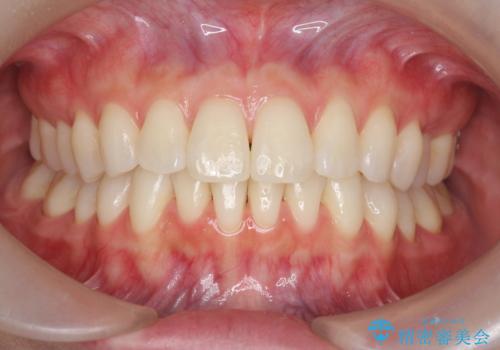

- 矯正治療後の後戻りを主訴に来院。

特に下の前歯のがたつきを気にされていました。

マウスピース矯正で再矯正を行いました。

再度の後戻りを防ぐため、下顎前歯の裏にはワイヤーを貼る保定を行っています。